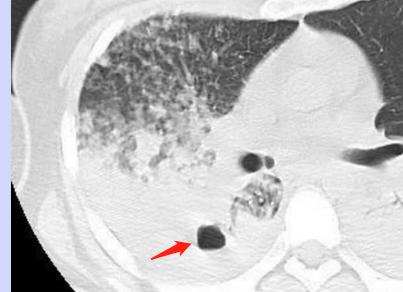

2.空洞:

结核杆菌感染引起肺组织坏死、液化,咳出后会形成局部空洞:

右下肺干酪性肺炎,形成空洞,周围大片磨玻璃影